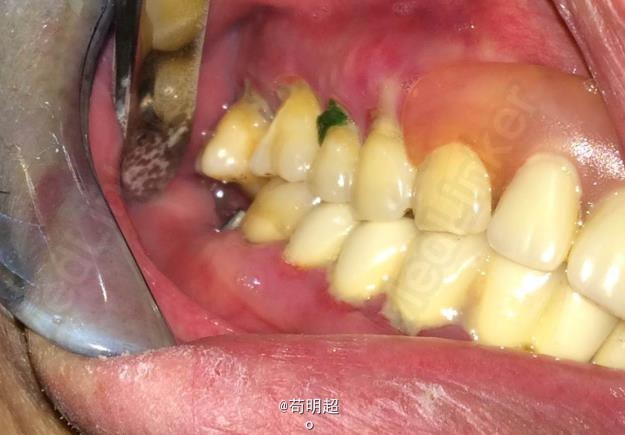

47牙齿种植修复

患者,男,40岁,47牙缺失要求种植。平素体质一般,无药物、食物过敏史,无高血压、心脏病等系统病史。